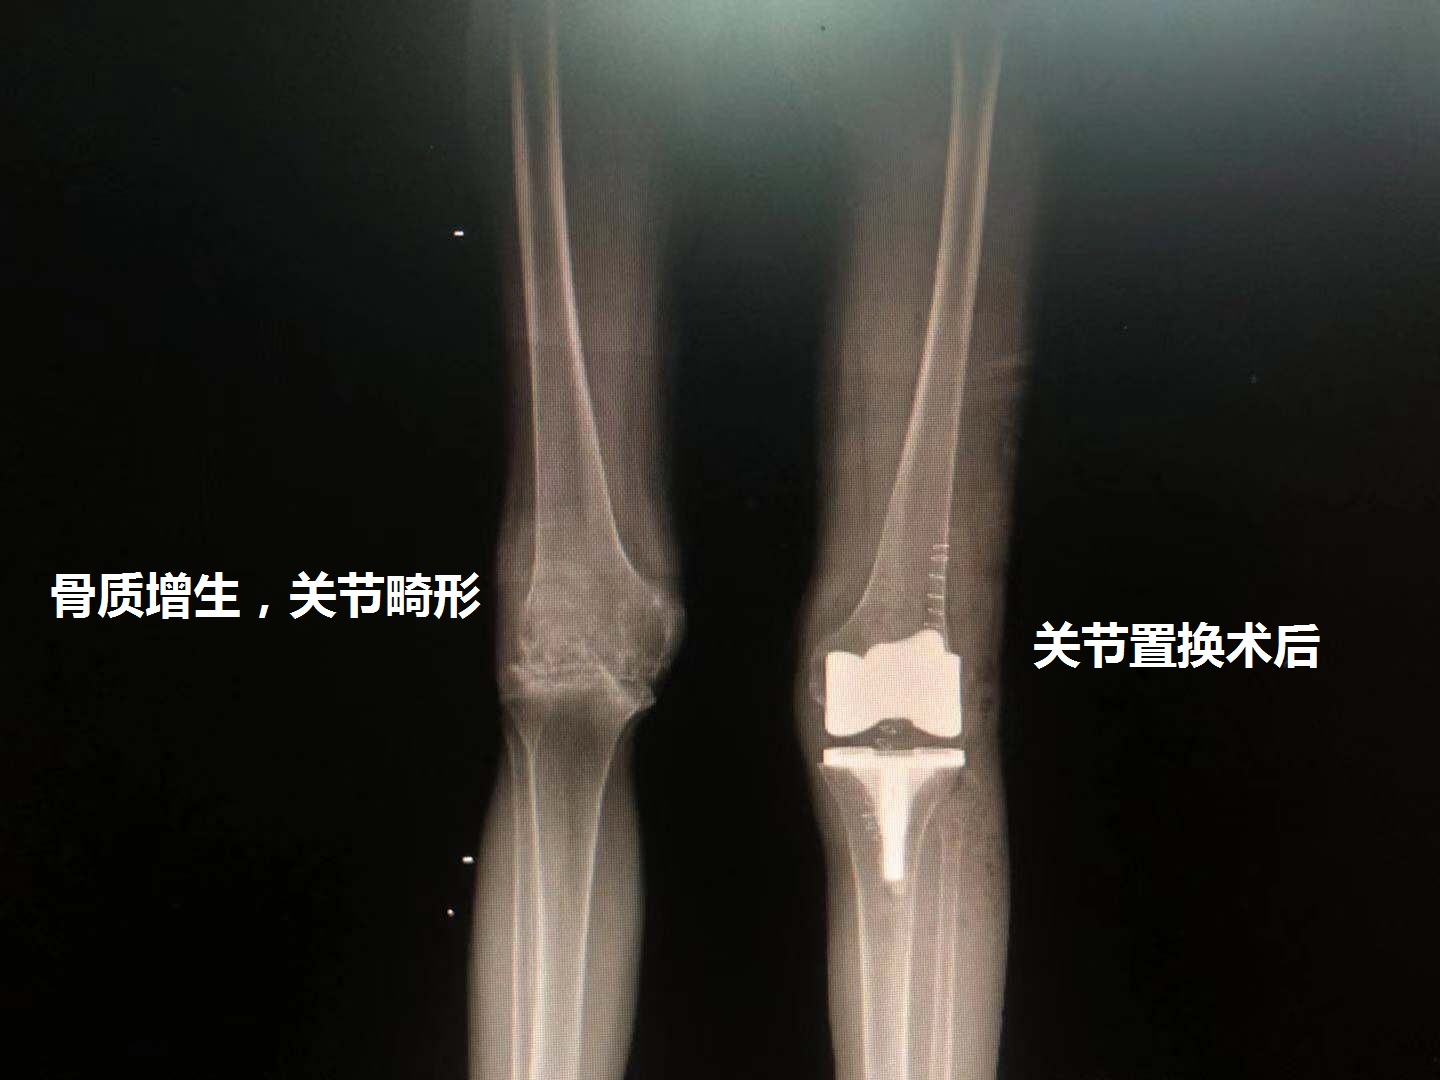

关节畸形:骨质增生、关节炎明显,膝关节已经出现明显的畸形。关节内的无菌性炎症因子会腐蚀关节内的组织,导致膝关节出现严重畸形,针对膝关节患者来说,膝盖没法弯曲跟伸直,关节活动度非常的差,针对这种病人来说,保守治疗已经基本没效果,再尝试保守治疗也可能于事无补!

总结:膝关节炎导致的骨质增生早期可以采用保守治疗为主,到后期关节活动受限、关节疼痛明显则考虑手术治疗,而手术不是单纯的去除骨质增生治疗,而是选择关节置换手术。